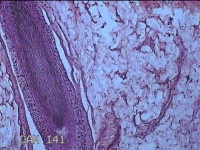

头部肿物

性别

男

年龄

21岁

临床诊断

头皮肿物

一般病史

发现头部结节10余年,无明显疼痛及不适。

标本名称

头部结节

大体所见

灰白暗红色带皮肤样结节1.5x1.3x0.3cm一个,切开结节呈实性,切面灰白粉红色,质软。